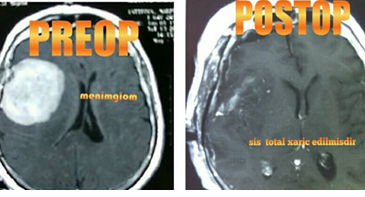

Xəstədə böyük ölçülü ŞİŞ - MENİNGİOM aşkar edildi və Op.Dr.RAUF SADIQOV tərəfindən...